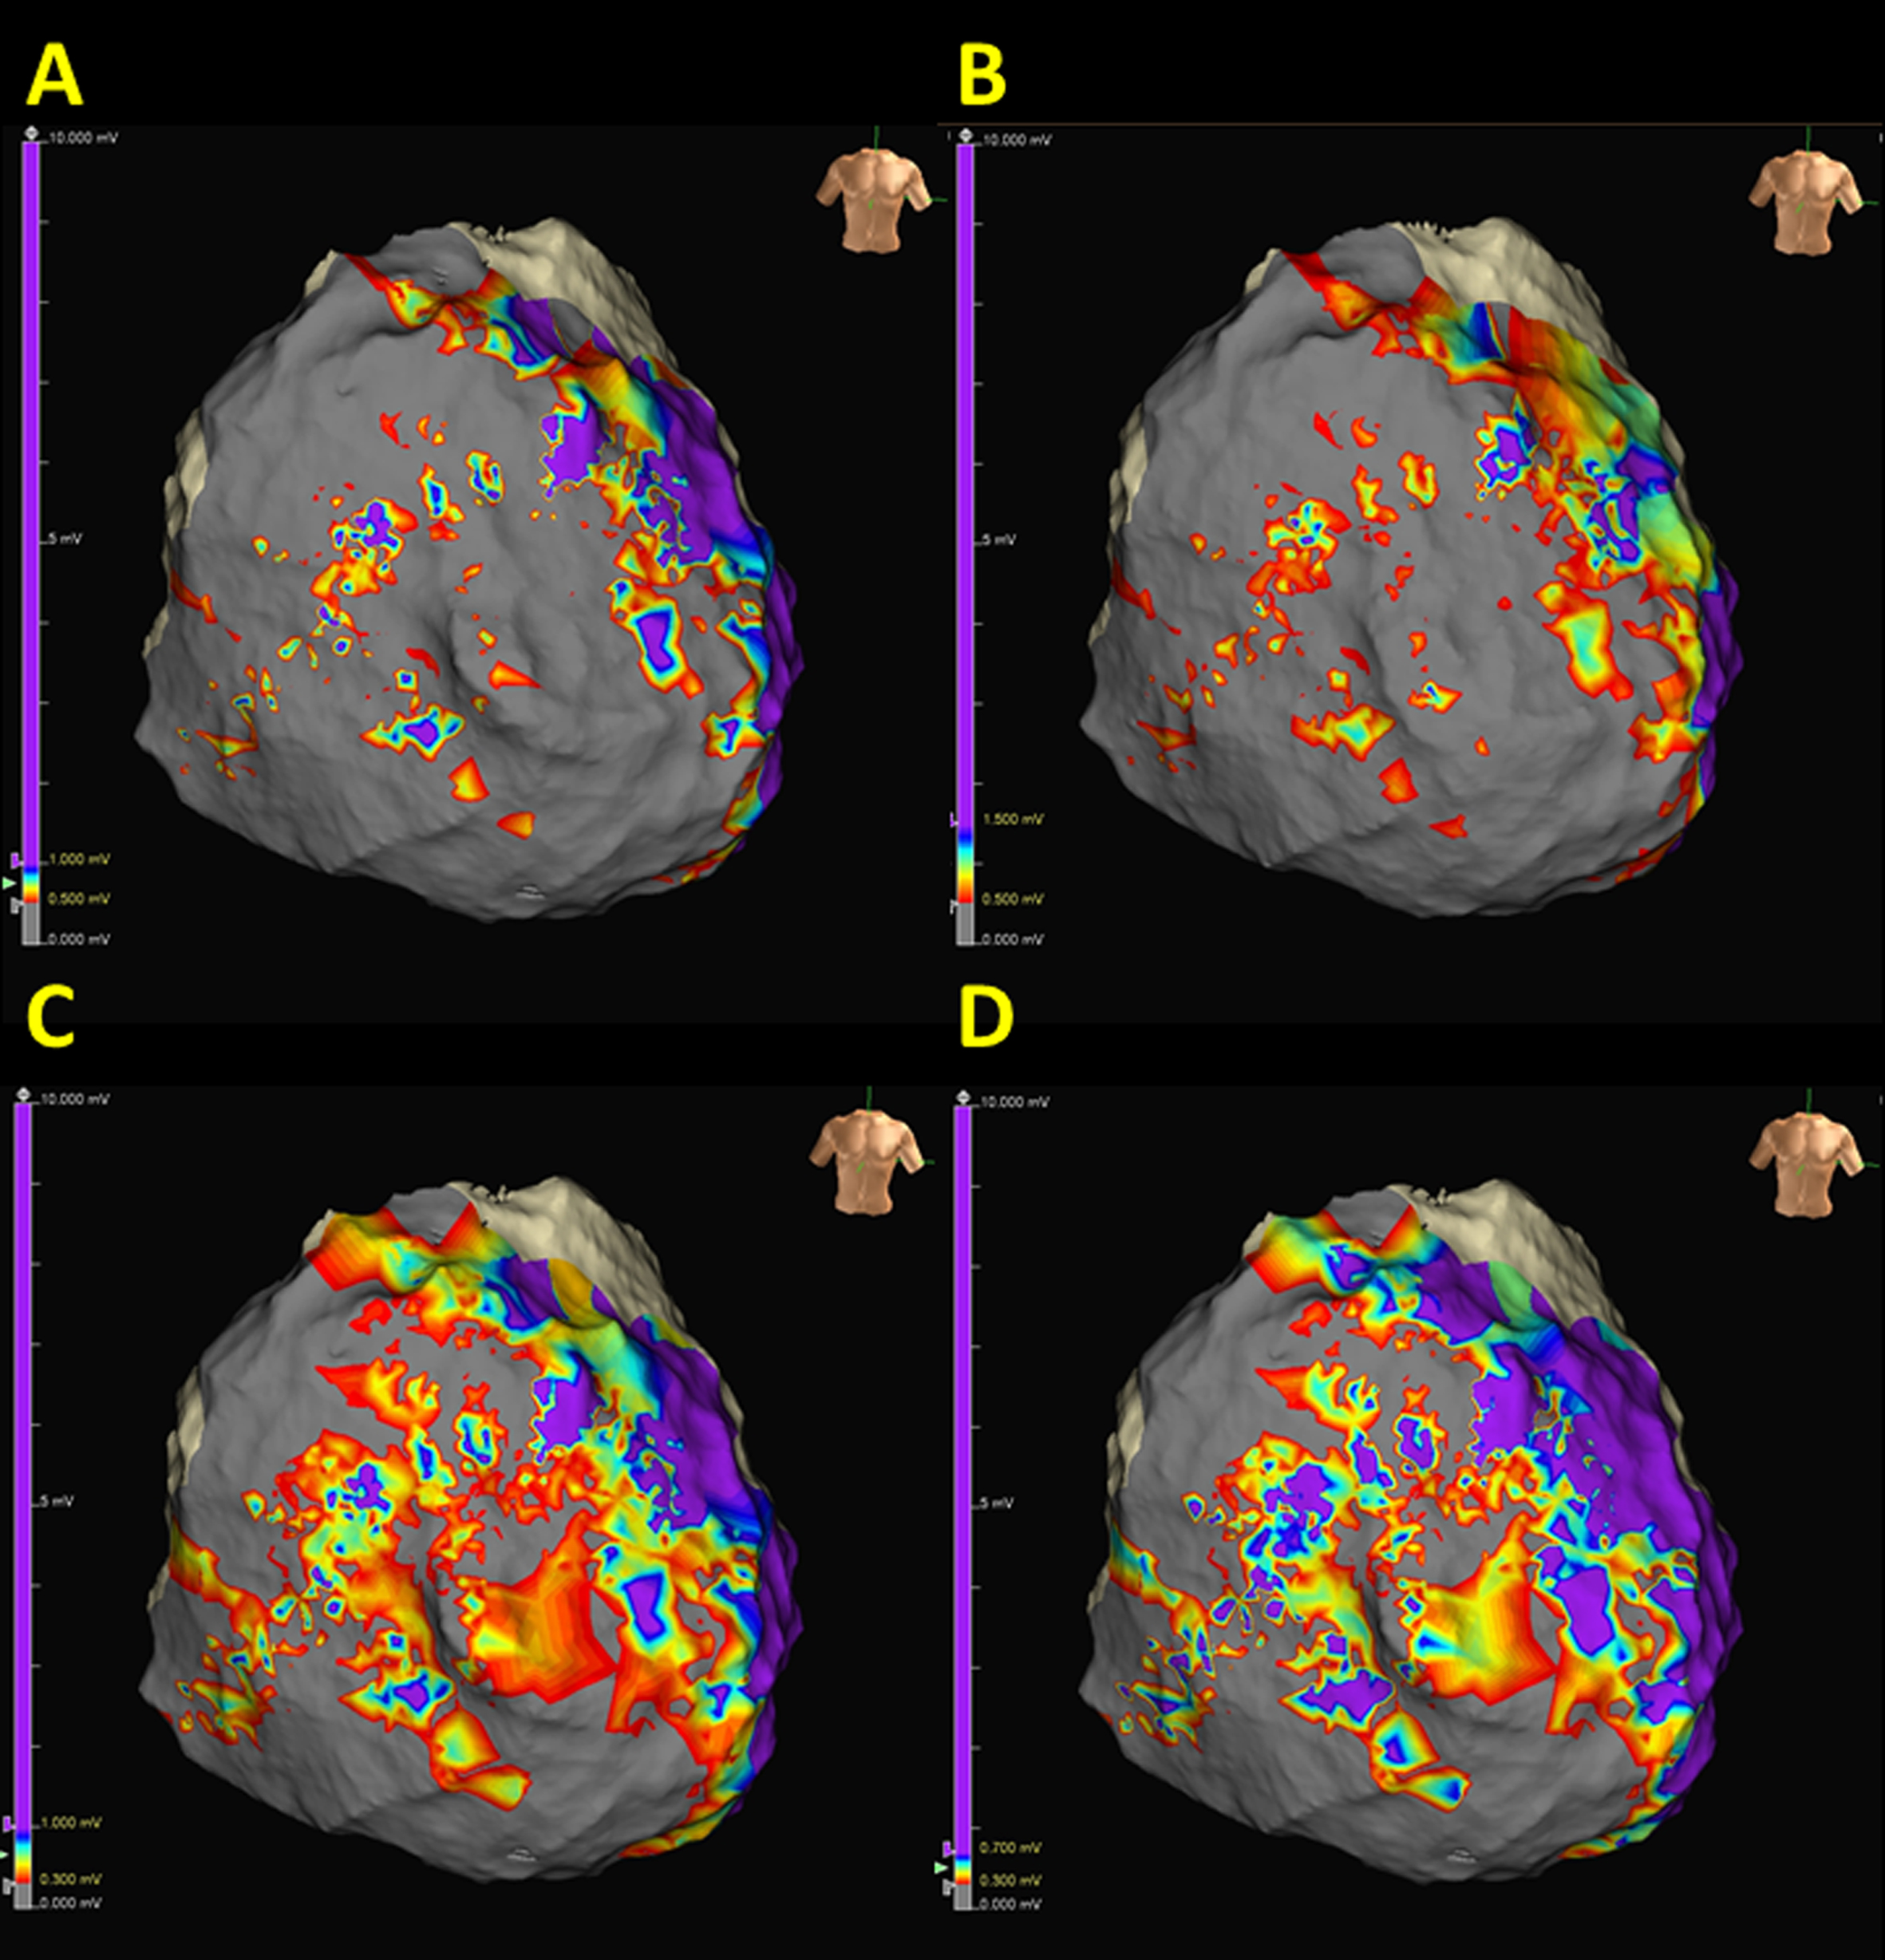

Fig. 1.

Fig. 1.Identification of potential epicardial channels by adjusting the bipolar voltage threshold. Possible channels could be observed within the superior tricuspid annulus, lower tricuspid annulus, and right ventricle (RV) free wall. Voltage thresholds were 0.5–1.0 mV, 0.5–1.5 mV, 0.3–1.0 mV, and 0.3–0.7 mV in (A–D), respectively.

In addition to the above, advances in high-density mapping using closely spaced multielectrode mapping catheters provide better delineation and higher resolution of ventricular scars [35, 36, 37, 38, 39]. Since the critical VT isthmuses responsible for clinically documented VT are usually complicated and frequently localized within dense scars, high-density mapping also yields a better illustration of channels within the scar [40]. However, the appropriate cut-off value of scarring, particularly in patients with ARVC, remains unknown and requires further investigation.